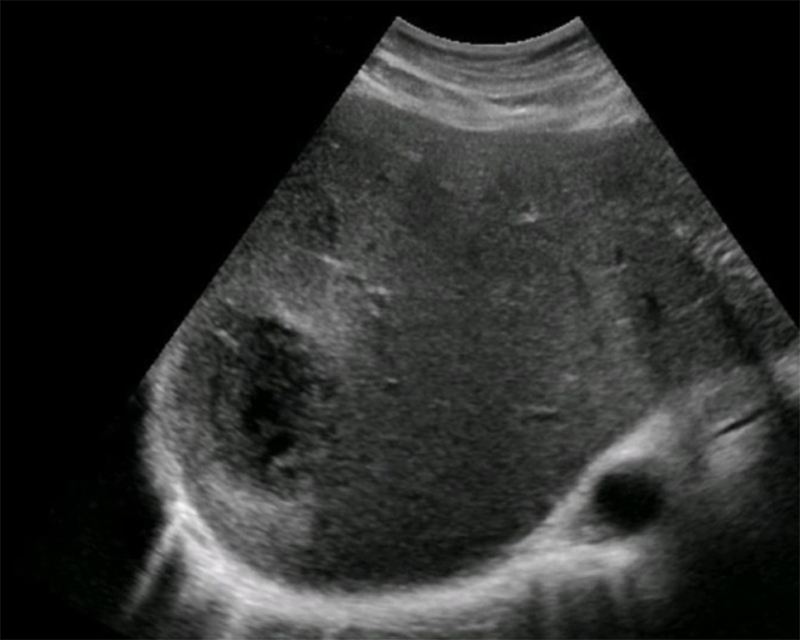

- Non-vertex (breech, transverse, or oblique) increases risk of difficult delivery and complication25

Figures 30A & B. Suprapubic views revealing no fetal cranium in the pelvis. While in some cases like this transverse view of a breech presentation (A) and this sagittal view of a transverse presentation (B), it may be difficult to exactly determine the fetal anatomy, the lack of the fetal cranium is adequate to rule out a vertex presentation and should increase the clinician’s suspicion for a more difficult delivery.